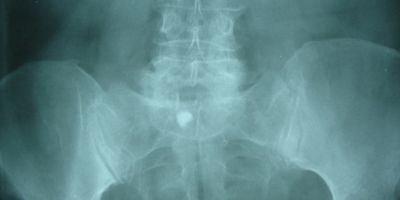

There are two major bursae in the hip that typically become irritated and inflamed. The greater trochanter covers the bony point of the hip bone. Inflammation of this bursa is called trochanteric bursitis.  The iliopsoas bursa is located on the inside (groin side) of the hip. Pain is often experienced in the groin area. This condition is not as common as trochanteric bursitis, but is treated in a similar manner.

The main symptom of trochanteric bursitis is pain at the point of the hip. The joint will often feel achy and stiff.  The pain usually extends to the outside of the thigh area. In the early stages, the pain is usually described as sharp and intense. Later, the pain may become more of an ache and spread across a larger area of the hip. As the problem progresses, the symptoms produce a limp when walking and stiffness in the hip joint. Eventually, the pain will also be present at rest and may even cause a problem with sleeping.